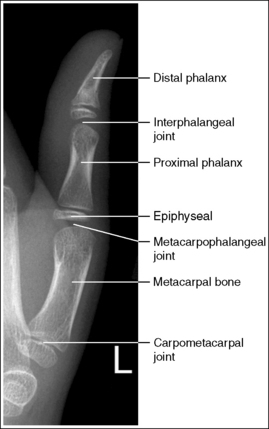

See Figure 4-10 and Box 4-4.

The digit of interest is in a lateral projection. The anterior aspect of the middle and proximal phalanges demonstrates midshaft concavity, and the posterior aspects of the phalanges show slight convexity.

• A lateral finger projection is accomplished by rotating the affected finger 90 degrees from the PA projection (Figure 4-11). Whether the hand is rotated internally or externally to obtain this goal depends on which direction will bring the finger closer to the IR. Typically, when the second and third fingers are imaged, the hand is rotated internally and, when the fourth and fifth fingers are imaged, the hand is rotated externally.

• Distinguishing lateral projection from rotated projection. To understand the difference between a truly lateral digit projection and a lateral projection that is rotated, study a finger skeleton in lateral and PA and AP oblique projections. Note how the midshaft concavity of the middle and proximal phalanges varies as the digit is rotated. In a lateral projection, the anterior aspect of these phalanges is concave, but the posterior aspect demonstrates slight convexity. In PA and AP oblique projections, both sides of the middle and proximal phalangeal midshafts demonstrate concavity, but the side toward which the anterior surface is rotated demonstrates a greater degree of concavity than the side toward which the posterior surface is rotated. The soft tissue width at either side of the phalanx also changes in the lateral and PA and AP oblique projections. More soft tissue is present on the side of the phalanges toward which the anterior surface is rotated (see Image 7).

The IP joints are visible as open spaces, and the phalanges are not foreshortened.

• The IP joints are open, and the phalanges are demonstrated without foreshortening as long as the finger was positioned parallel with the IR and the central ray was perpendicular to and centered with the PIP joint.

The PIP joint is at the center of the exposure field. The distal, middle, and proximal phalanges and the metacarpal head of the affected digit are included within the collimated field.

• Center a perpendicular central ray to the PIP joint to place it in the center of the image. Open the longitudinal collimation to include the distal phalanx and the metacarpal head. Transversely collimate to within 0.5 inch (1.25 cm) of the finger skin line.